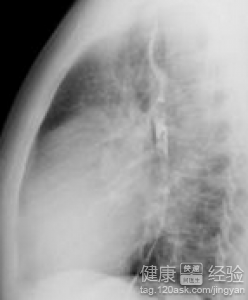

首先做不做手術這個問題我想要告訴你的是,所有的手術都是有風險的。尤其是心髒方面的疾病更是如此,不過手術治療確實是治療風濕性心髒病的最重要的手段之一。風濕性心髒病由於風濕熱的原因,導致心房顫動造成的疾病,患者在得了風濕性心髒病之後會出現胸口疼痛,胸悶氣短,呼吸困難,四肢無力,出汗,昏迷休克,嚴重的甚至會死亡的嚴重後果。

1目前來說,治療風濕性心髒病的最有效的方法還是手術,因為通過手術,可以及時的切除病變部位,緩解風濕性心髒病病情,患者也可以在家裡准備一些抗心髒的疾病也是可以治療的。

由於風濕性心髒病是一種危險性很高的疾病,患者在平時一定要做好個人的身體檢查,除了手術治療,藥物治療,心理治療。中醫調理等也可以治療風濕性心髒病。